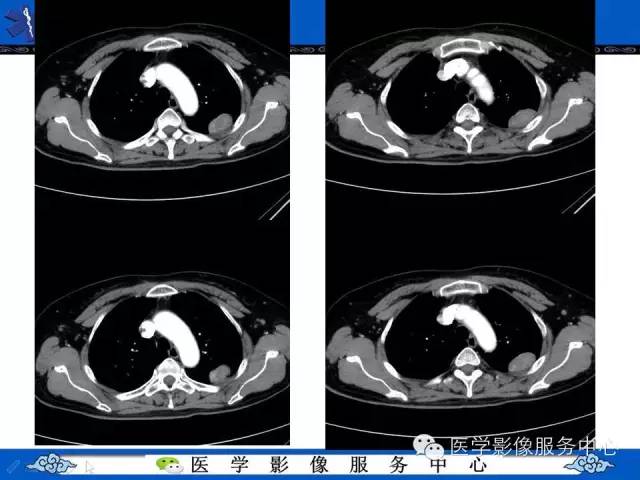

胸膜孤立性纤维瘤1例CT影像表现与鉴别

【病例】胸膜孤立性纤维瘤1例CT影像表现与鉴别